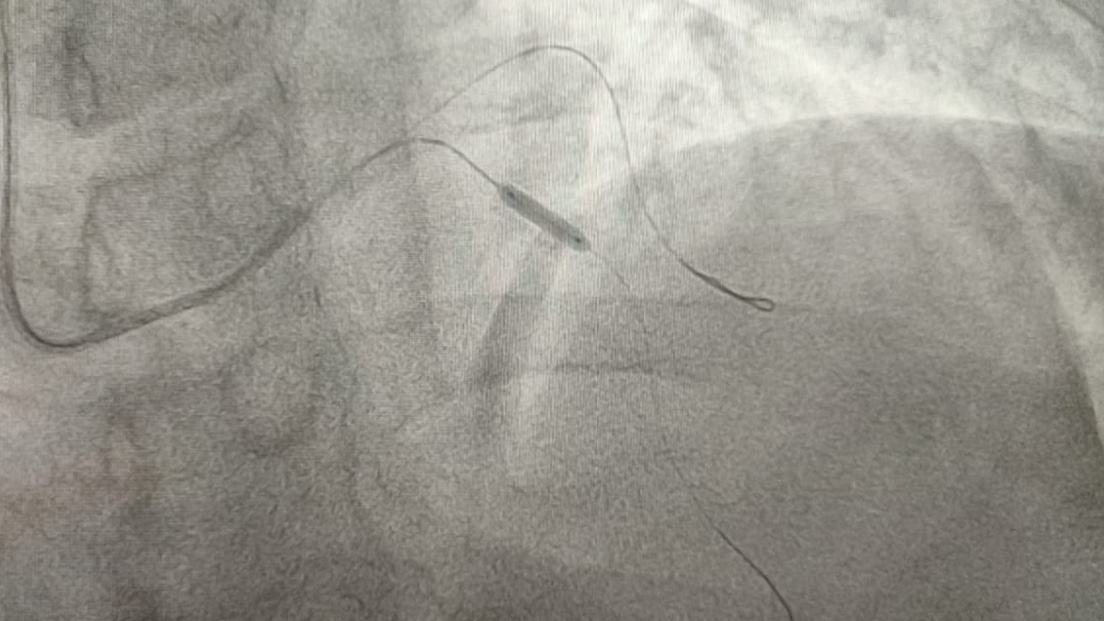

A través de un procedimiento de angioplastia coronaria y la colocación de estents en la nueva Unidad de Hemodinamia, se logró abrir las arterias que tenía obstruidas y restablecer su flujo de sangre.

Con la activación del “Código Infarto”, el equipo multidisciplinario de la nueva Unidad de Hemodinamia se puso en marcha, e inició medicamento para deshacer el coagulo del paciente y darle recepción para la apertura de la arteria que se encontraba obstruida al 90 por ciento, lo cual impedía el paso de sangre al corazón.

Al culminar el procedimiento, se destapó la arteria, se colocó un medicamento especial para evitar una nueva oclusión y, de esta manera, el paciente recibió una nueva oportunidad de vida.